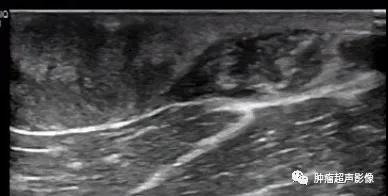

病理证实的隆突性皮肤纤维肉瘤:上臂隆起于皮肤表面的无痛肿块,呈紫红色,形态不规则,水平方向生长,内回声不均(见不规则条带状高回声与低回声相间隔),血流稍丰富。